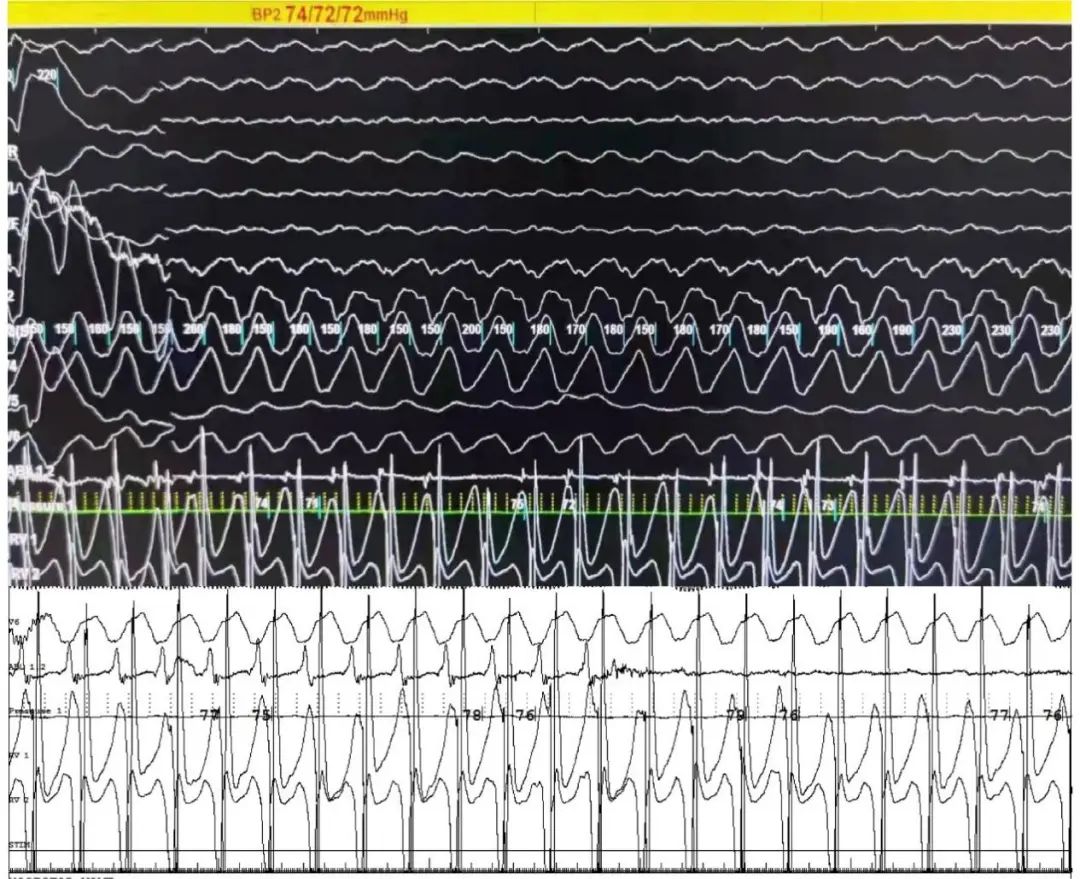

图片

术中室速发作, 患者心室率高达270bpm,心脏停止有效射血,有创血压的压力波形曲线(绿色曲线)消失ECMO支持下平流血压72mmHg